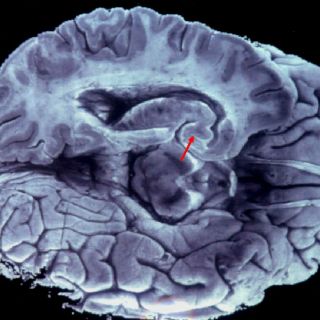

El comunicado refiere que gracias a las imágenes del cerebro obtenidas mediante tomografía computarizada o resonancia magnética, se puede observar la disminución de las neuronas o el desarrollo de proteínas conocidas por favorecer al alzhéimer.